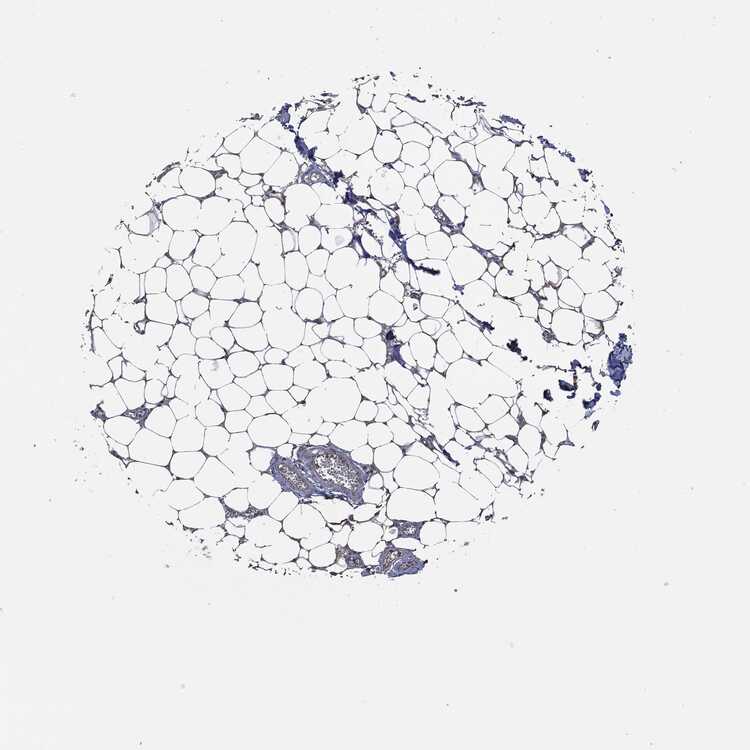

SOFT TISSUE 1 - Antibody stainingi

Antibody staining in the annotated cell types in the current human tissue is reported as not detected, low, medium, or high, based on conventional immunohistochemistry profiling in selected tissues. This score is based on the combination of the staining intensity and fraction of stained cells.

Each image is clickable and will lead to virtual microscopy that enables deeper exploration of all samples and also displays staining intensity scores, fraction scores and subcellular localization as well as patient and tissue information for each sample.

Antibody HPA017172Antibody CAB002216Antibody CAB080356

Chondrocytes Medium-Medium

Fibroblasts Not detectedNot detectedLow

Peripheral nerve Not detectedNot detectedNot detected